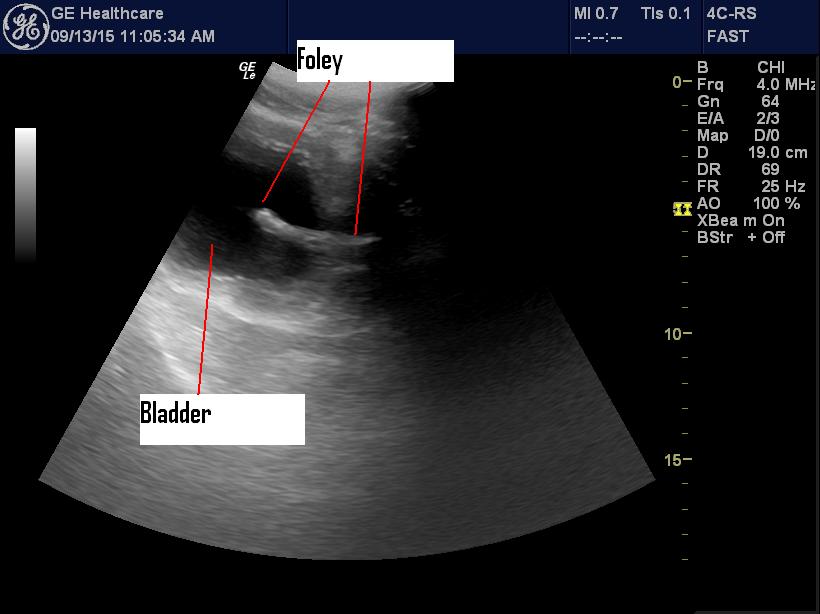

The nurses put a Foley in and drained a lot of urine but couldn’t

inflate the Foley balloon. I had a look and there was no Foley in the

bladder.

I pushed it in a few centimeters and sure enough the Foley appeared in

the bladder.